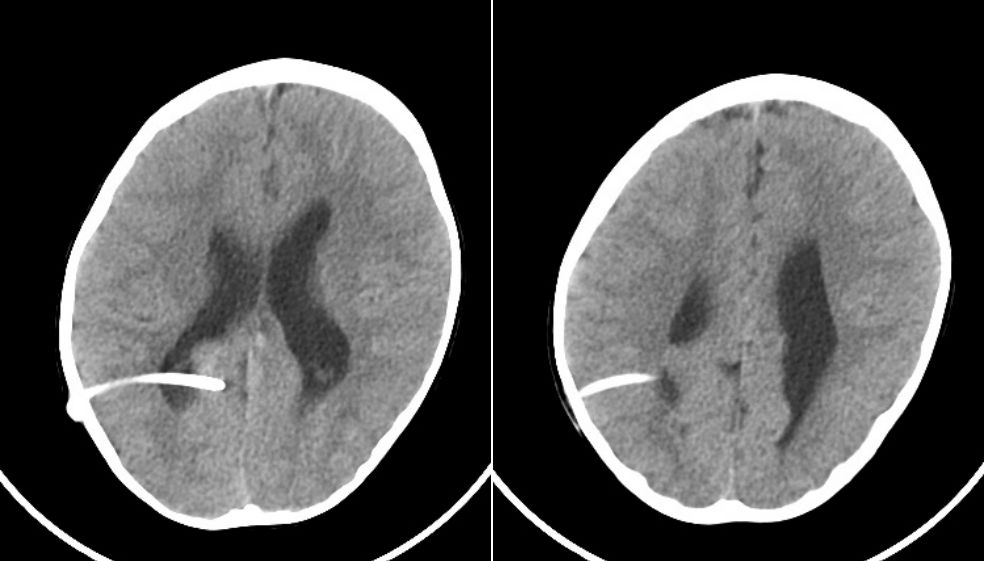

病例1,头颅CT及MRI检查提示:幕上脑室扩张,皮层菲薄,第四脑室形态正常。梗阻性脑积水,导水管部位梗阻可能。(图1)。

图1.头颅CT及MRI检查提示:幕上脑室扩张,皮层菲薄,第四脑室形态正常。梗阻性脑积水,导水管部位梗阻可能。